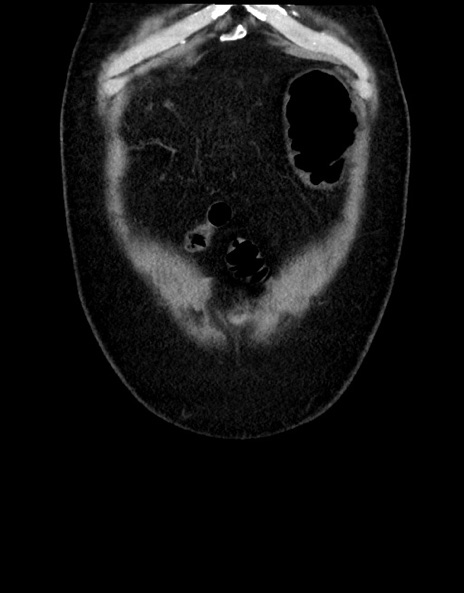

横断像